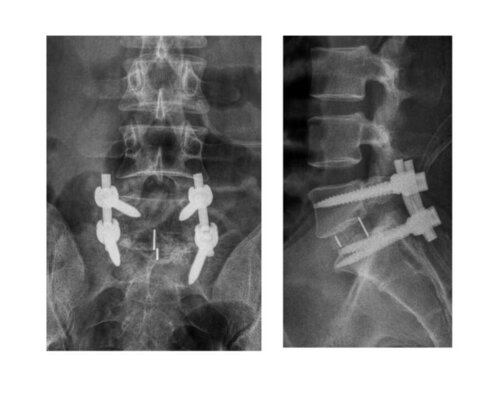

Successful Spine Surgery by Dr. Shailesh Deshmukh in Baner

Dr. Shailesh Deshmukh, a distinguished orthopedic surgeon in Baner, Pune, recently treated a 48-year-old male patient with a disc lesion and listhesis...